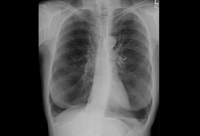

Radiografia torácica de deficiência de alfa 1-antitripsina (AAT) (visualização póstero-anterior [PA])

Da coleção pessoal de D. Kyle Hogarth, MD, FCCP; usado com permissão